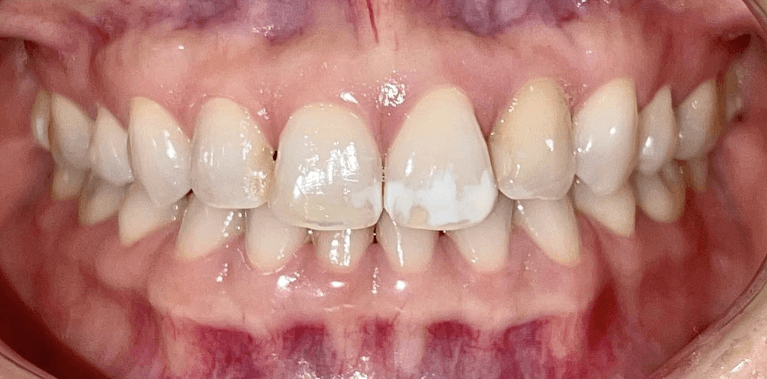

White spot treatment with Icon and mild spacing correction with Invisalign(5weeks only)

Sometimes it’s the little things that matter the most.